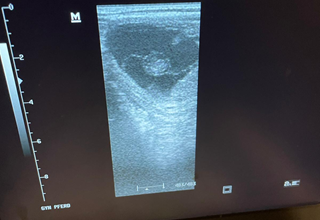

Wir bieten umfassende Betreuung rund um die Fortpflanzung und Trächtigkeit von Stuten – von der Zyklusdiagnostik bis zur Geburt.

„Eine erfolgreiche Zucht erfordert Erfahrung, Präzision und Geduld. Wir begleiten Stutenbesitzer von der Bedeckung bis zur Geburt – zuverlässig, fachlich fundiert und pferdegerecht.“